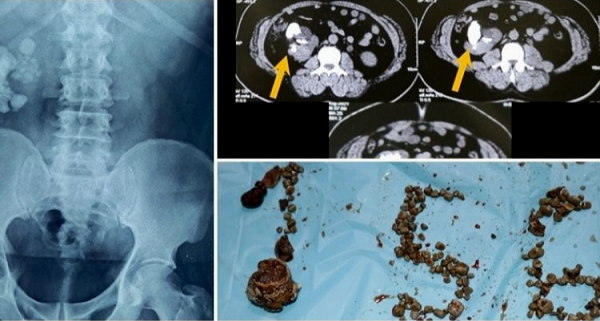

हैदराबाद। तेलंगाना में हैदराबाद के एक अस्पताल के डॉक्टरों ने 3 घंटे की सर्जरी में 50 साल के एक मरीज की किडनी से 156 पथरी (स्टोन) निकालीं। डॉक्टरों ने कहा कि, भारत में किसी मरीज से निकाले गए पत्थरों की यह सबसे बड़ी संख्या है। मरीज एक स्कूल शिक्षक है, जो पेट के दर्द से परेशान था। उसने अपनी जांच कराई तो स्क्रीनिंग में किडनी में बड़ी संख्या में स्टोन पाए गए।

डॉक्टरों ने उस मरीज किडनी को यूरिनरी ट्रैक्ट में सामान्य स्थिति के बजाय पेट के पास स्थित पाया। जिसके बाद डॉक्टर उसके इलाज में जुट गए। उनके तीन घंटे तक चलने वाली निष्कर्षण प्रक्रिया में लैप्रोस्कोपी और एंडोस्कोपी शामिल थी। प्रीति यूरोलॉजी और किडनी अस्पताल के प्रबंध निदेशक और मूत्र रोग विशेषज्ञ डॉ चंद्र मोहन ने कहा, "हमारे यहां 3 घंटे तक चली प्रक्रिया के बाद पथरी को मरीज के शरीर से पूरी तरह से निकाल दिया गया। शरीर पर एक बड़े कट के बजाय, एक साधारण कट लगाकर, पेट के अंदर बड़ी संख्या में एकत्रित हुईं पथरी (पत्थरों) को निकाला गया।''

डॉ चंद्र मोहन ने आगे कहा, ''अब मरीज स्वस्थ और सकुशल है। वह अपनी नियमित दिनचर्या में वापस आ गया है। वैसे उसके पेट में इतनी बड़ी संख्या में स्टोन (पत्थरों) देखकर एक बार तो हम हैरान रह गए थे। हालांकि, हमारे डॉक्टरों की सतर्कता और उच्च तकनीक की सहायता से उन पत्थरों को कम समय में ही पूरी तरह से निकालने में मदद मिली।,"

पता चला है कि, हुबली के रहने वाले मरीज के पेट में इतनी पथरी थी। जिसके बाद उसे प्रीति यूरोलॉजी और किडनी अस्पताल में भर्ती कराया गया था। जिसके बारे में डॉक्टरों का कहना है कि भारत में किसी मरीज से निकाले गए किडनी स्टोन की यह सबसे बड़ी संख्या है।